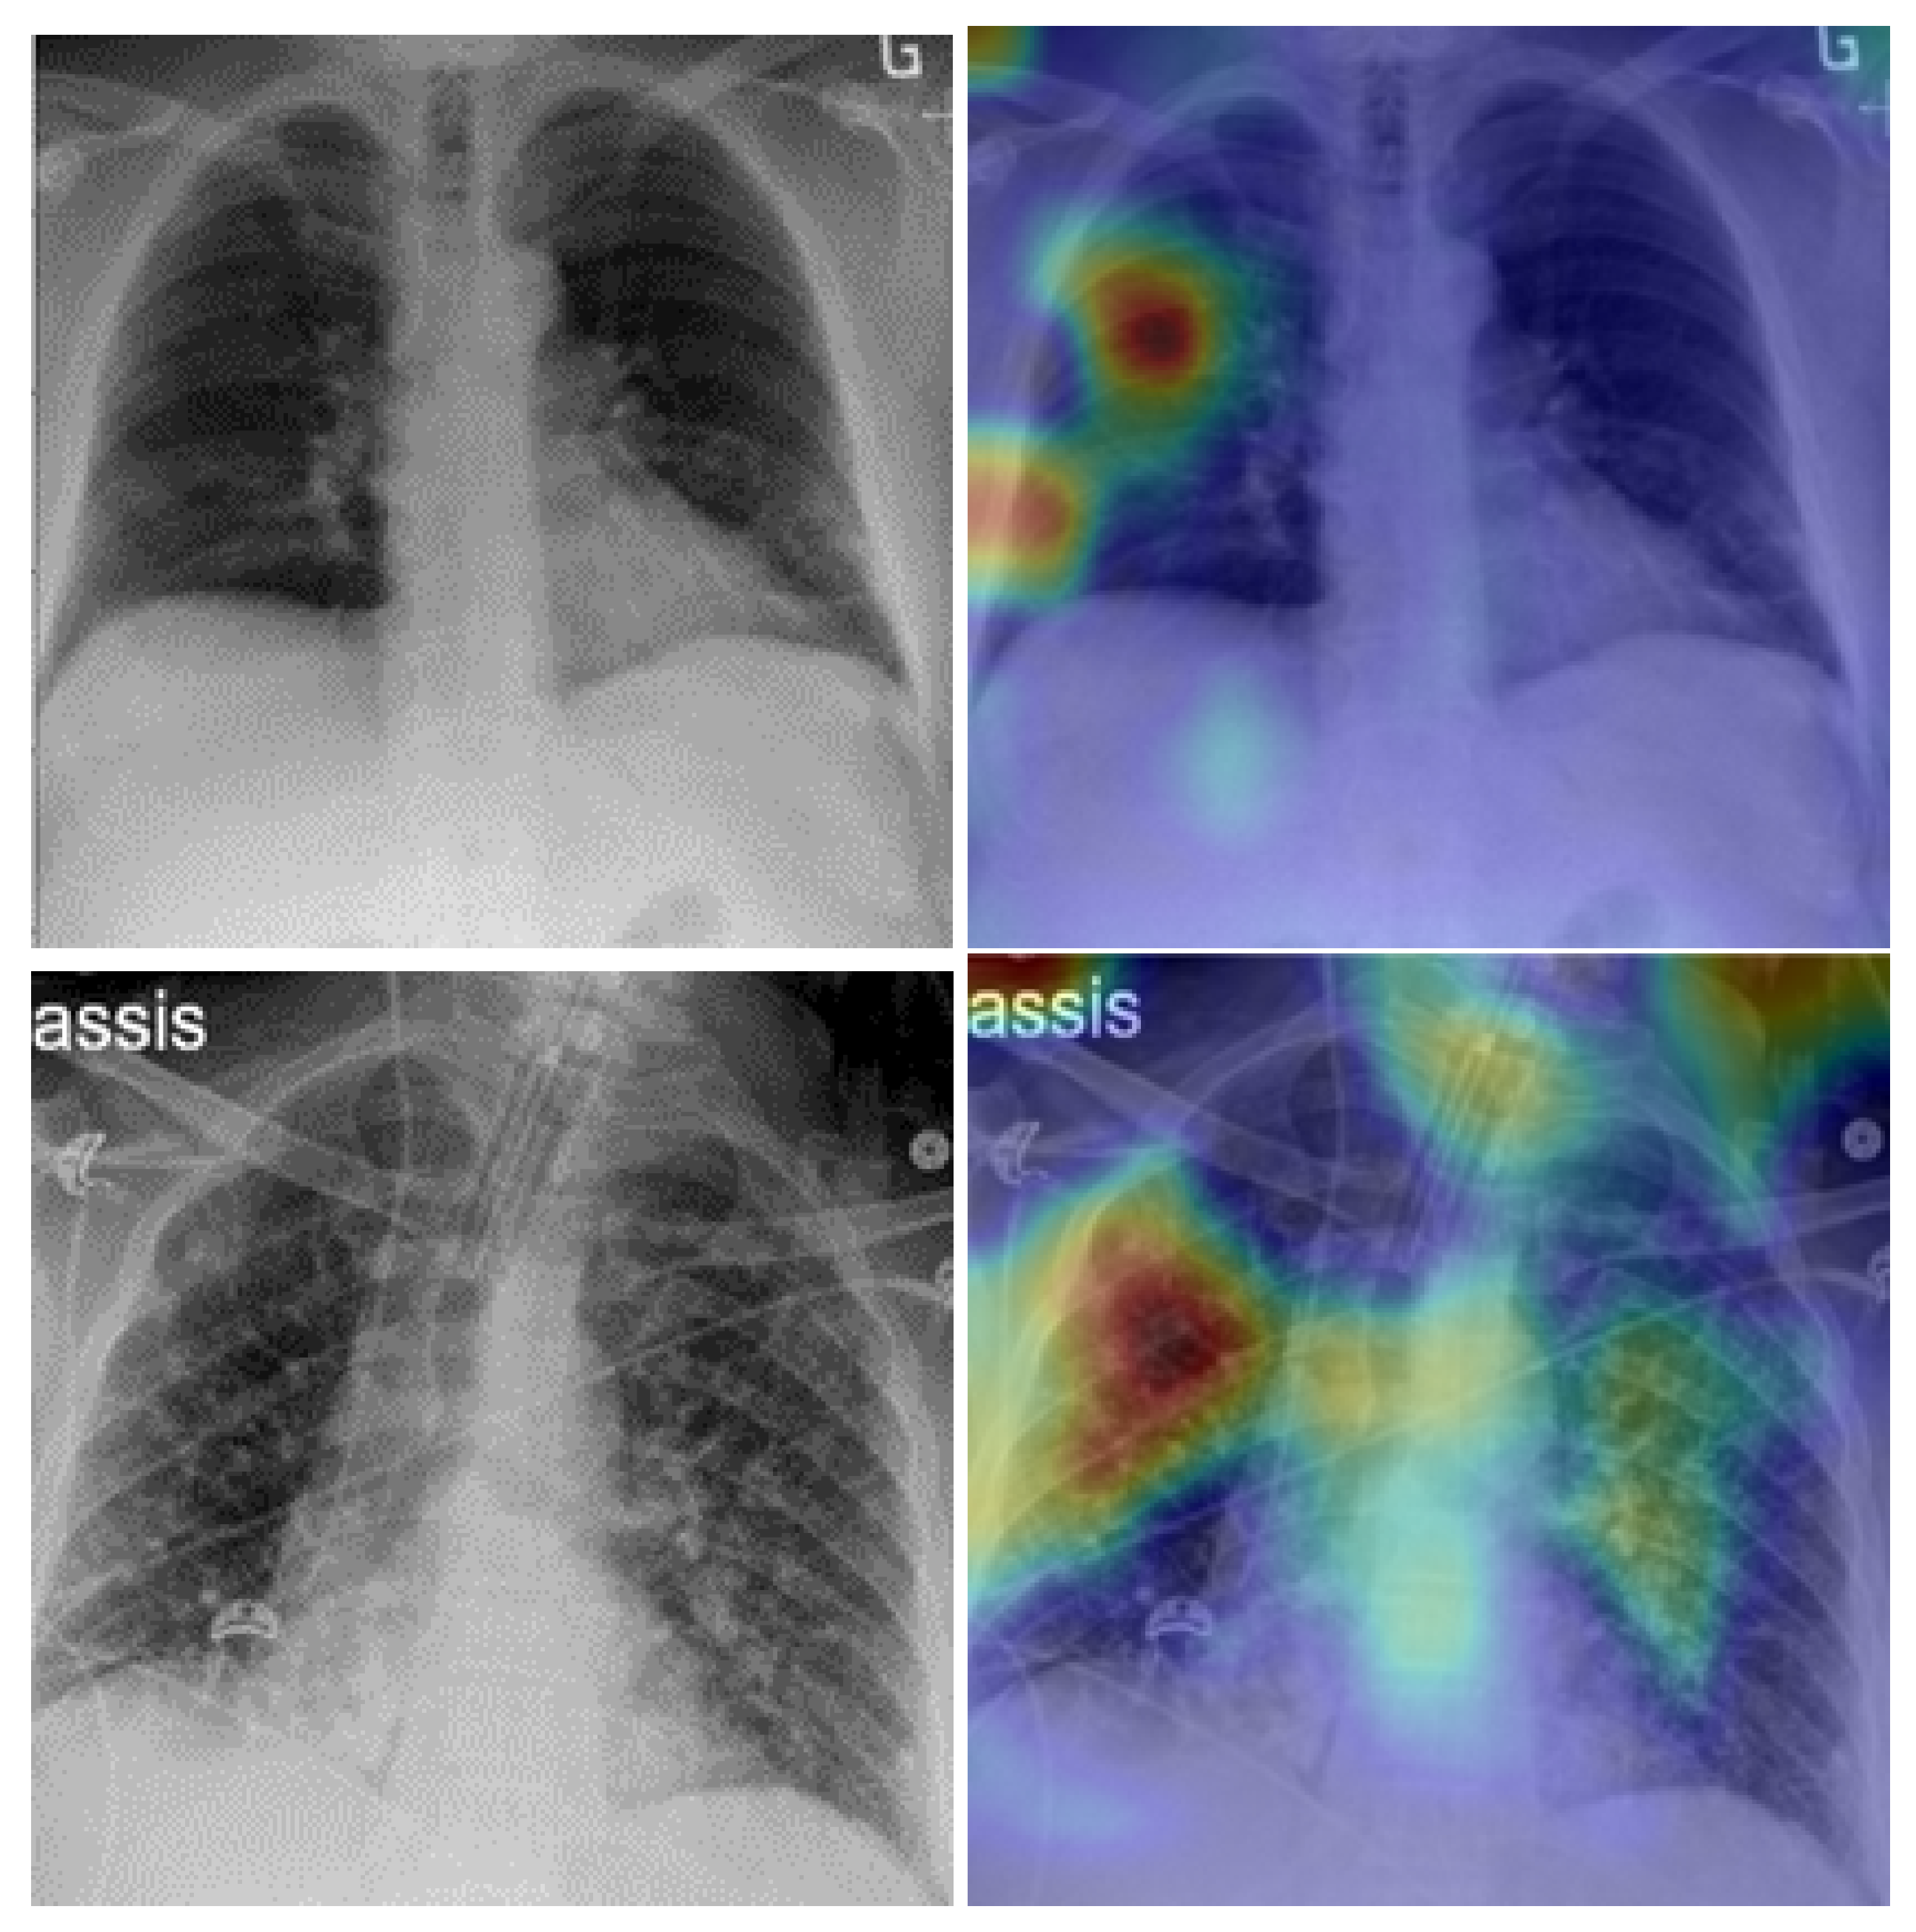

5. Model Explainability